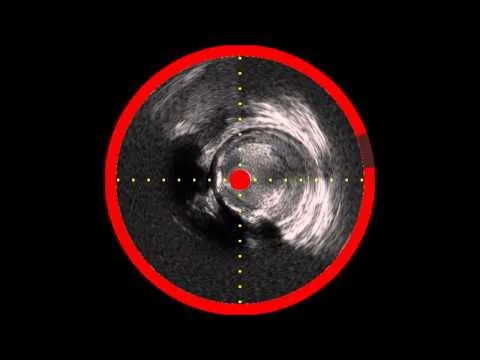

Zilver PTX after Viance cross, with Infrared-X IVUS to Confirm Stent Expansion